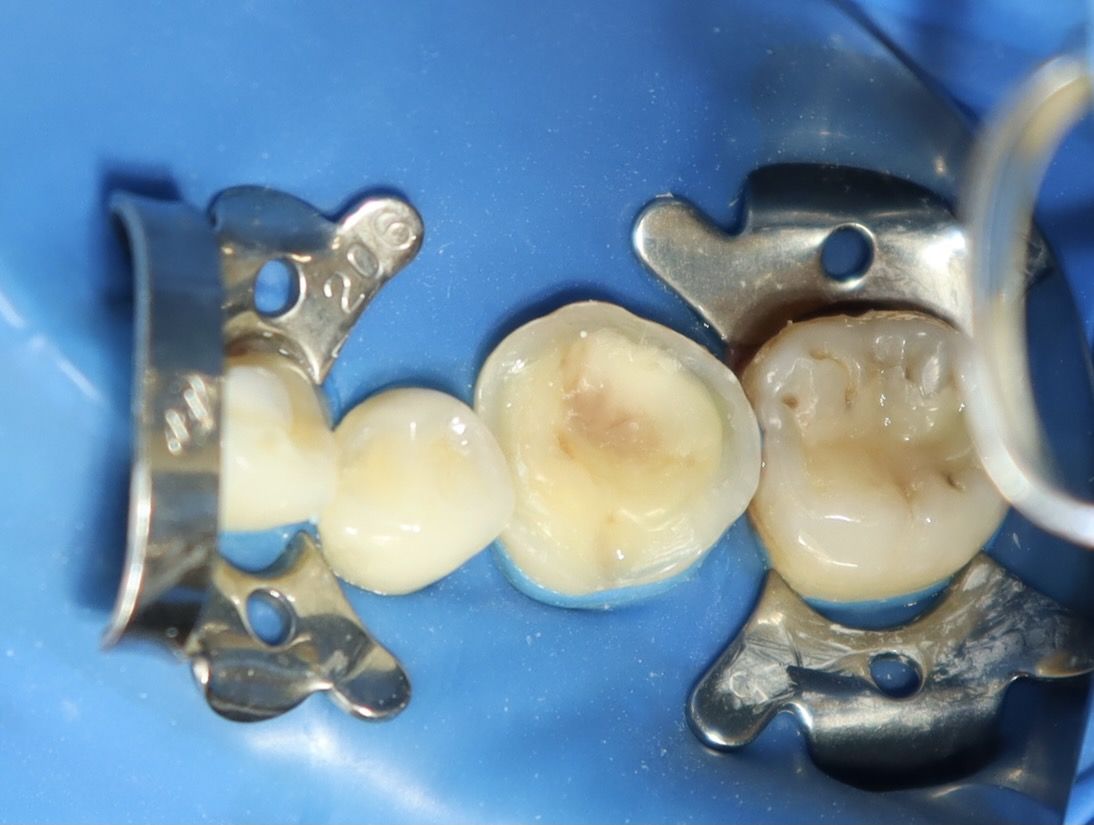

術後照片

術中照片